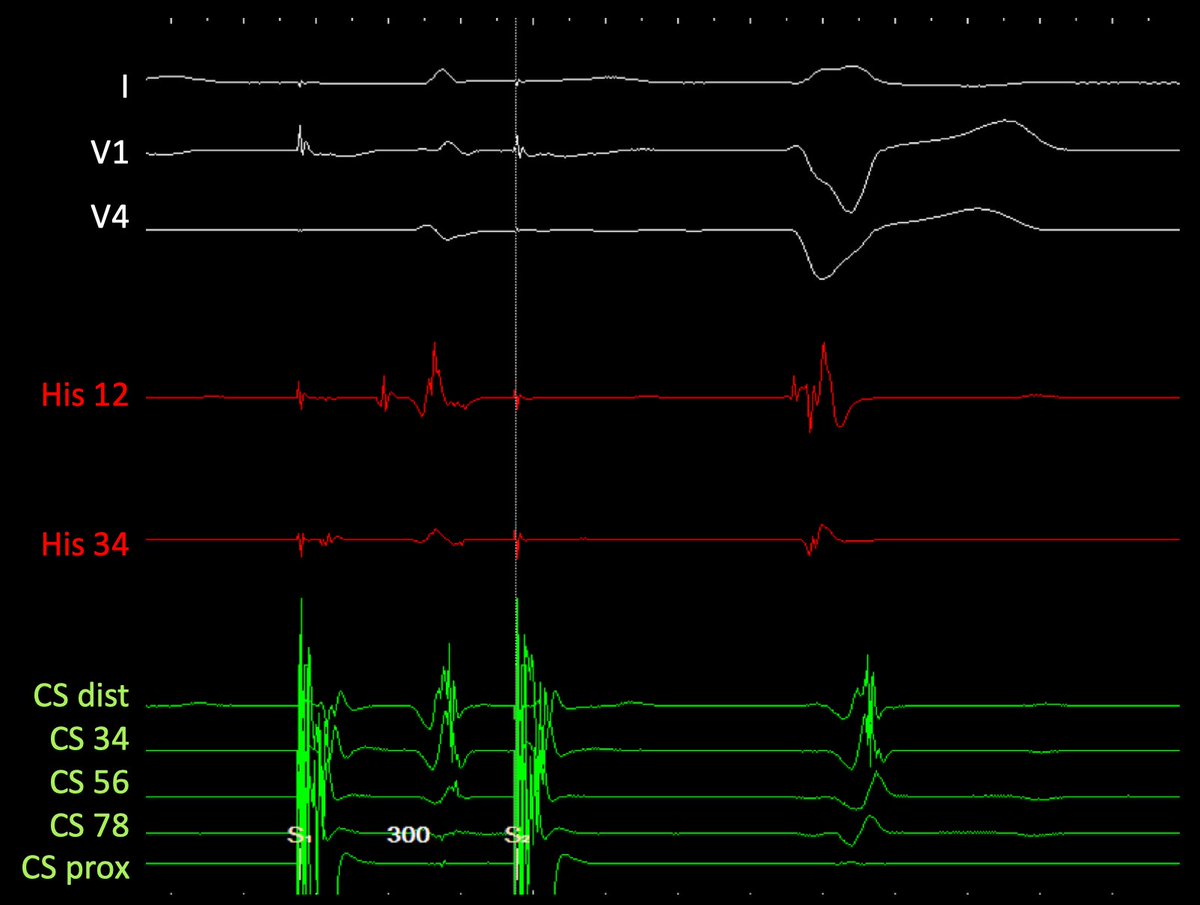

Almost incessant JET alternating with bigeminated junctional premature beats (most of them with anterograde block). Mapped during JET. Yellow dots=His area. Red area: earliest atrial activation. Succesfully ablated 5 mm away from his (20W). Thanks to @AlemunozAR for the map.